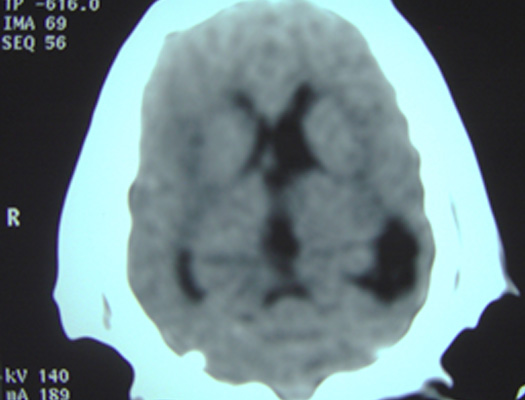

Sarita comienza a presentar signos de incremento de la presión intracraneana (PIC) en forma progresiva. Se le realiza una tomografía cerebral de urgencia observando presencia de hidrocefalia asimétrica marcada y presencia de zonas hiperdensas asimétricas en materia blanca de corteza cerebral.